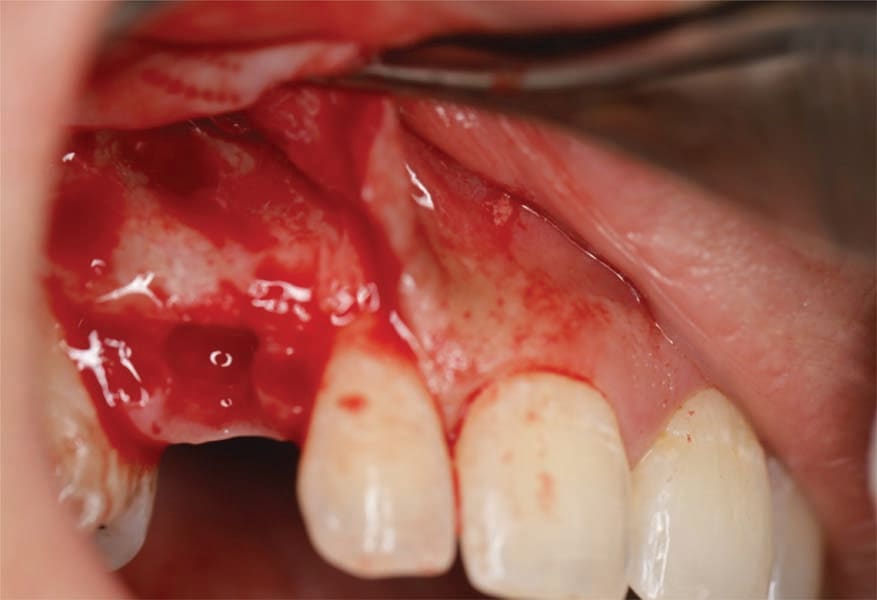

The patient presented for extraction of the deciduous canines and block grafting of the sites. Consent forms were reviewed with the patient and were signed. Local anesthetic was administered at the sites. Teeth C and I were extracted atraumatically, and a full-thickness mucoperiosteal flap was elevated at those sites (Figure 6). In this patient cortico-cancellous block grafts bilaterally were chosen (Puros® J-Block, ZimVie). The block of bone was contoured first on the cancellous alveolar side, with a football-shaped bone bur. The bone was placed in the recipient bed and was held firmly; the rest of the contouring was performed on the cortical side to allow the block to fit the site. Minimizing the thickness of the cortical bone also reduces the risk of dehiscence of the area. The cortical side was reduced significantly to allow adequate penetration of blood to allow integration and remodeling to native bone but leaving sufficient cortex to support adequate fixation. Next, using a 1.2-mm drill, the recipient site was thoroughly perforated to allow fresh bleeding and adequate penetration of the blood cells and growth factors into the graft. The graft then was firmly held against the recipient site, the 1.2-mm drill was used to place the screw hole, and a 1.2-by-10-mm screw was used to the secure the block graft into place (Figure 7). This was repeated at the left canine site (Figure 8). Particulate graft was not added so that the periosteum was in direct contact with the block to allow faster vascularization of the block graft. The periosteum underneath the flap was thoroughly scored and the flap was advanced to achieve tension-free primary closure and secured with 4-0 Vicryl sutures (Figure 9). The patient was seen for follow-up 1 week post-surgery.